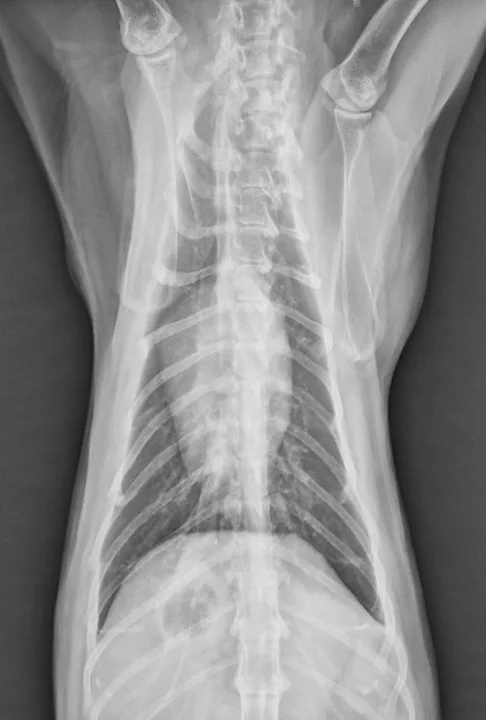

Figure 2

Dorsoventral radiograph of right-sided caudal primary lung tumor. Image courtesy of Rachel Moon, DVM, DACVR

Reported primary lung tumors (Figures 1 and 2) include squamous cell carcinoma and sarcoma, but adenocarcinomas are reportedly the most common histopathologic diagnosis.2 Adenocarcinomas are subcharacterized by location (ie, bronchial, bronchioloalveolar, alveolar) and grade. Carcinomas are graded on histopathology as differentiated or undifferentiated, with the grade directly correlating with metastatic incidence.1,3 Although most primary carcinomas are localized and solitary at diagnosis,1,4 the literature suggests that >50% of undifferentiated carcinomas and 90% of squamous cell carcinomas metastasize,1,3 with one study reporting ≈75% of feline lung tumors as metastatic.4 Metastasis to the lungs, skin, CNS, and digits may occur transpleurally, hematogenously, or via lymphatics or airways.1,3,4